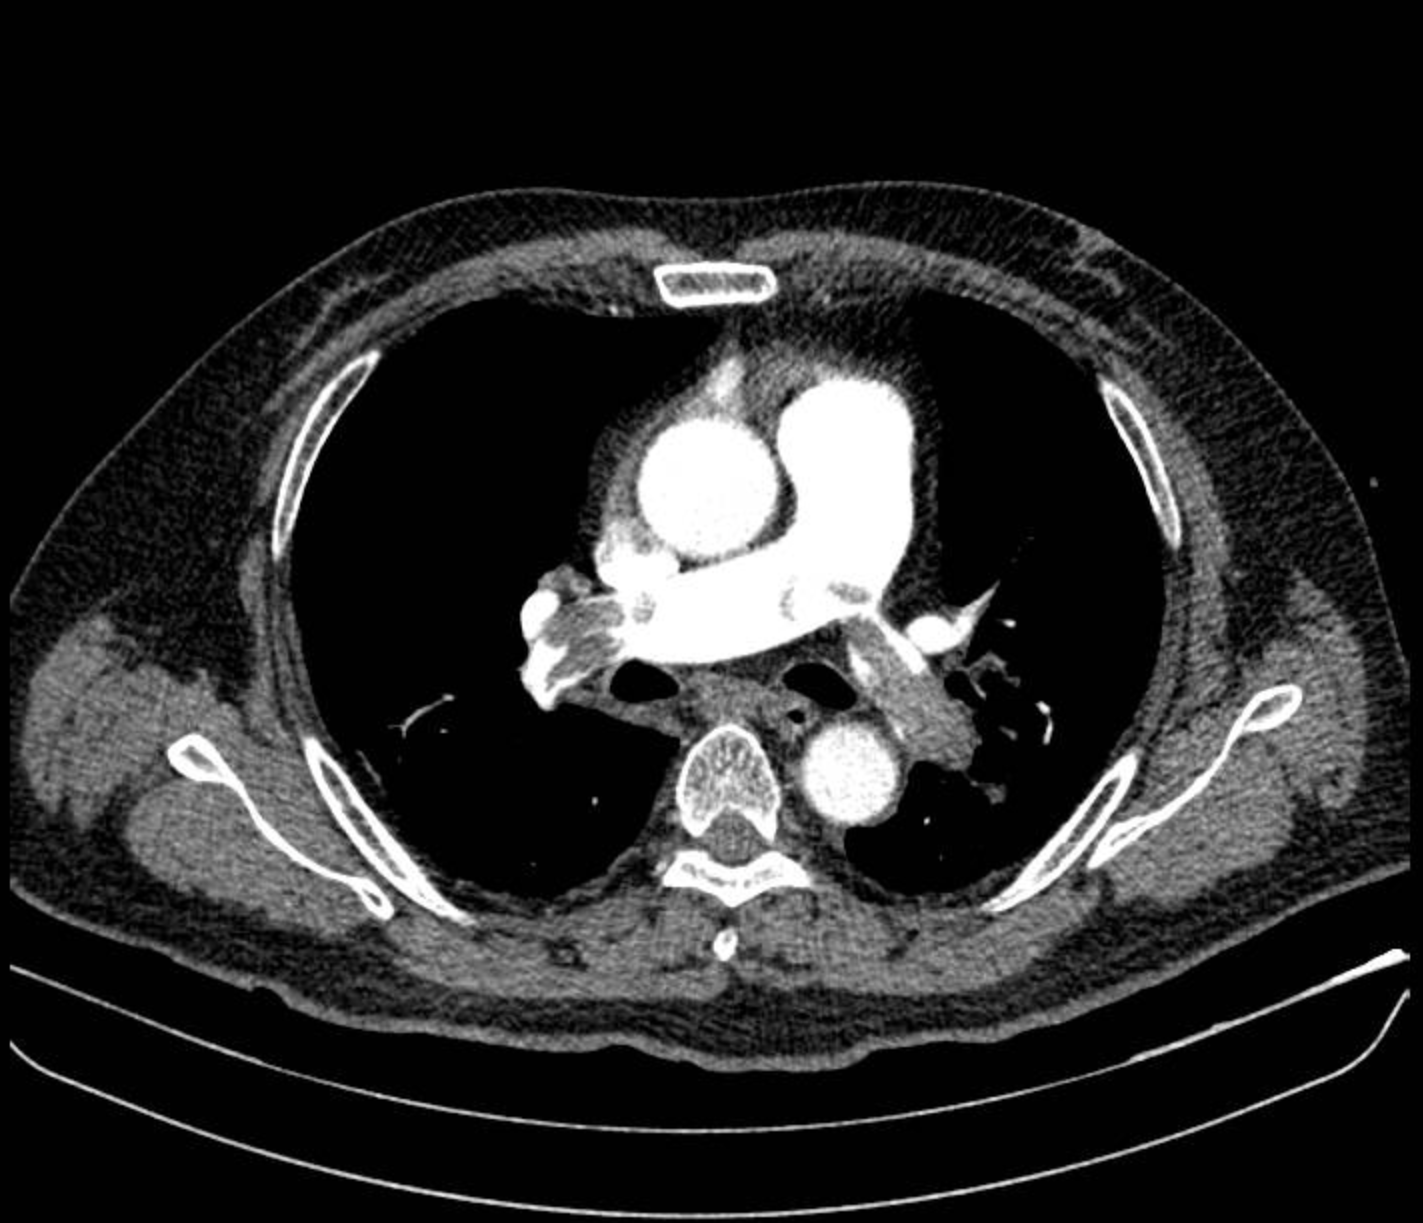

Kết quả điện tim và siêu âm tim cho thấy dấu hiệu quá tải thất phải cấp, điển hình của thuyên tắc phổi nặng. Ông L được dùng thuốc vận mạch ổn định huyết áp, sau đó chụp CT mạch máu phổi phát hiện huyết khối lớn bít tắc động mạch phổi hai bên.

Nam bệnh nhân được chẩn đoán sốc tắc nghẽn do thuyên tắc phổi nguy cơ cao và được điều trị bằng thuốc tiêu sợi huyết. Sau 1 tuần điều trị, ông L hồi phục tốt, huyết áp ổn định, hết khó thở, chức năng tim phải cải thiện rõ.